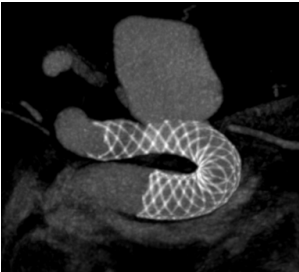

3.颈部和颅内动脉血管狭窄

最主要的病因是动脉粥样硬化。主要包括颈内动脉狭窄、大脑中动脉狭窄、椎动脉狭窄或者基底动脉狭窄等,常见的后果便是发生缺血性脑卒中。脑血管介入治疗(球囊扩张术、支架成形术等),就是通过股动脉将球囊送至狭窄部位,扩张球囊,再根据血管状况决定是否放置支架,即可将已呈现硬化、狭窄的动脉撑开,从而达到改善脑血流的治疗目的。